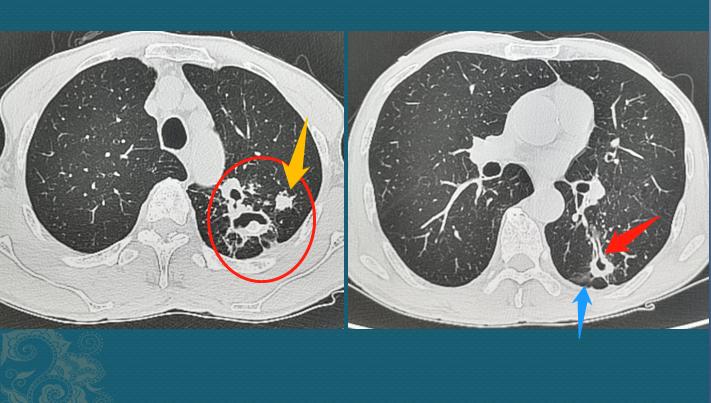

1.肺结核造成肺组织坏死液化,经支气管咳出脓痰后,在病变肺叶形成空洞,常可见引流支气管(红箭头),并且由于结核性炎症,支气管壁增厚。上图红箭头所指的黑色小管状结构,就是增厚的引流支气管。

2.多发小结节簇集(烟花征)、树芽征、小叶中心结节、磨玻璃影(蓝箭头)、反晕征、肺实变、伴有中心坏死的结节或肿块等;

像这个年轻的病人,有多发黑色的空洞,引流支气管壁增厚,有边缘模糊的结节影,有肺实变,是典型的活动性肺结核,有传染性,痰液中查到大量结核杆菌,要注意与家人保持隔离,不能随地吐痰。